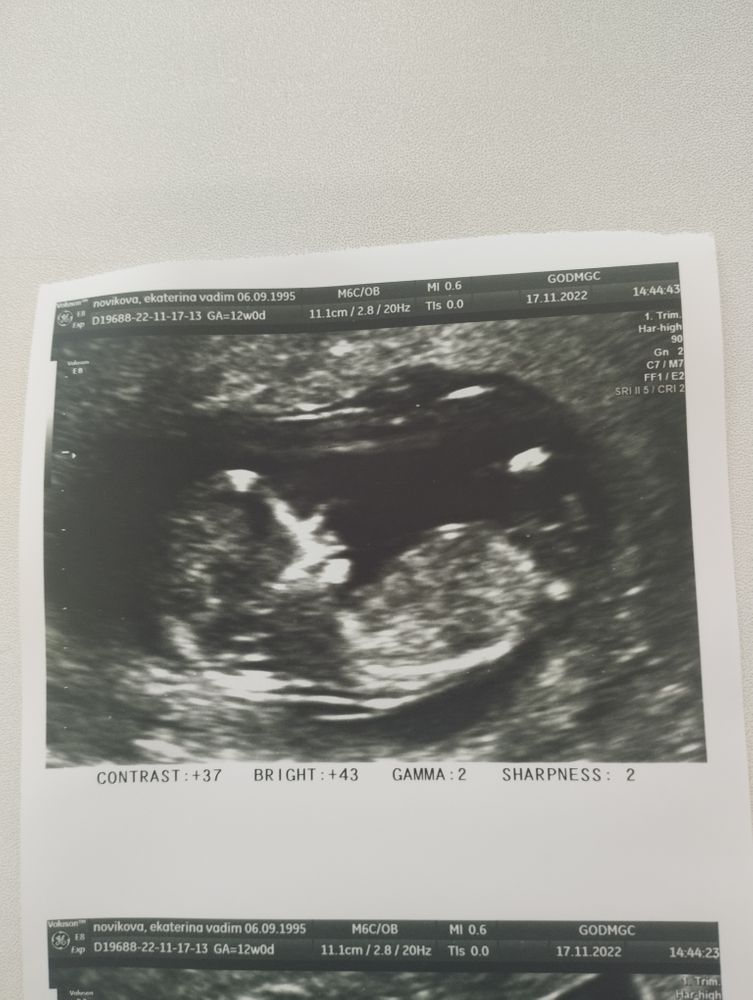

Сегодня был 1 скрининг, по УЗИ всё просто чудесно, опережаем срок 🥰 По месячным 12.0, по УЗИ 12.3.

Вот такой уже большой человек) Пол сказали рано 😆